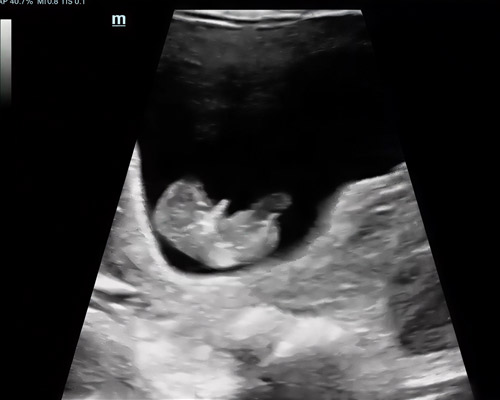

A reassurance scan is an ultrasound carried out during pregnancy to check on your baby’s wellbeing between routine appointments. Many parents choose this scan when they want extra peace of mind or simply wish to see their baby again.

During the appointment, the sonographer looks at key aspects such as the heartbeat, movements, activity levels, and position. This type of scan helps confirm that everything is progressing as expected.

For many families near Wakefield, this scan also offers a comforting experience. It gives parents a chance to reconnect and enjoy seeing their baby moving on screen, which can be both reassuring and memorable.

You will be able to see your baby’s movements, heartbeat, and position on the screen during the appointment.